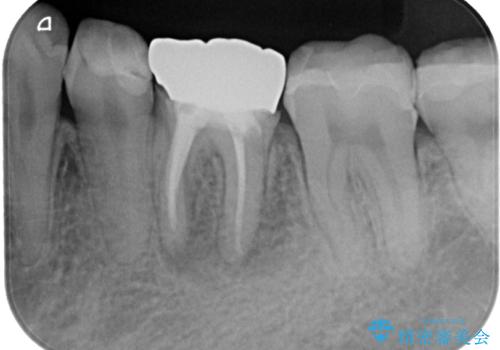

- 奥歯の詰め物が外れてしまったとのことで来院された患者様です。

幾度も詰め物治療を行ったため継ぎ接ぎだらけとなっていたため、インレーにて修復治療をすることとしました。

咬合力が強いため、ゴールド合金(PGA)のインレーを選択することとしました。

ゴールドインレーは銀歯のインレーやセラミックインレーと比べ、「技工操作の精度が高く、適合が著しく良い」というメリットがあります。特に上の奥歯は歯科医師の操作が行いにくいため、「適合の良さ」は再治療のリスクを防ぐ上でとても重要な要素となります。